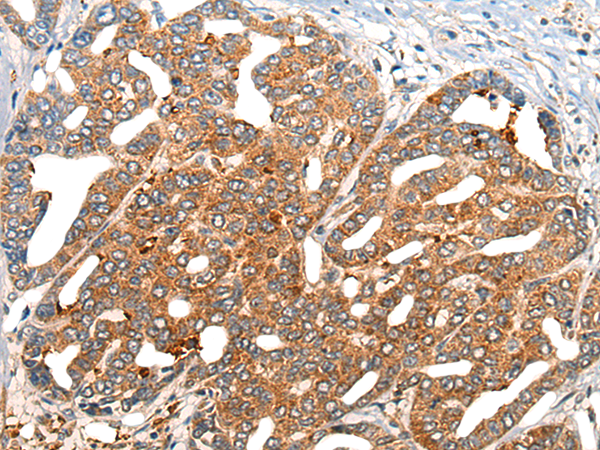

分类: 科研抗体货号: P13200别名: CLL1; MICL; CD371; CLL-1; DCAL-2应用: IHC反应种属: Human